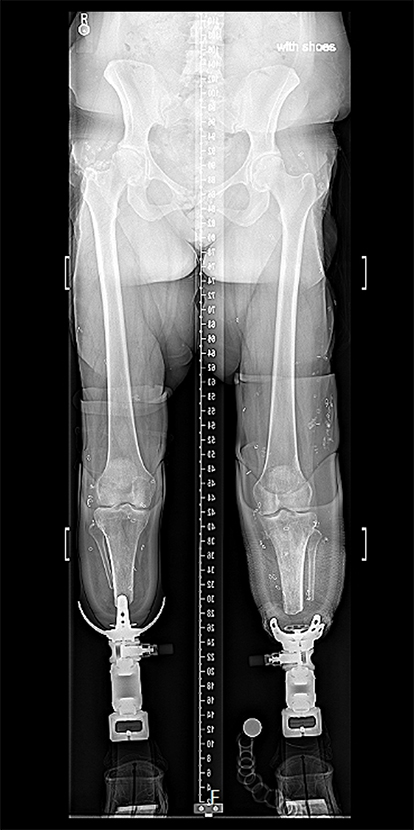

She reported constant aching and dull pain rated at 5/10, worsened by standing, walking, stair climbing, and performing daily activities, that improved with rest and activity modification. She had struggled with sockets and reported no phantom limb pain. Clinical examination found extensive scarring and skin grafts over bilateral tibias and femurs, with fissuring and tight, shiny skin. Small pressure wounds were noted on the left stump and on the medial aspect of the right stump. She had full extension of both knees with flexion to 100° on the right and 110° on the left. She had full power, no instability, and no neurological deficits. X-rays showed approximately 12 cm residual tibia bilaterally, with no deformity in the tibia, knee joint, or femur (Figure 2).

Figure 2. X-ray of patient’s bilateral lower limbs with patient standing in socket prostheses.